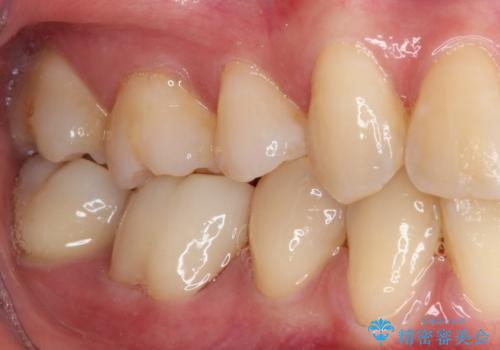

速やかに処置を進めたことで症状は落ち着き、治療後しばらくの状態では神経を取り除く可能性は低くなりました。